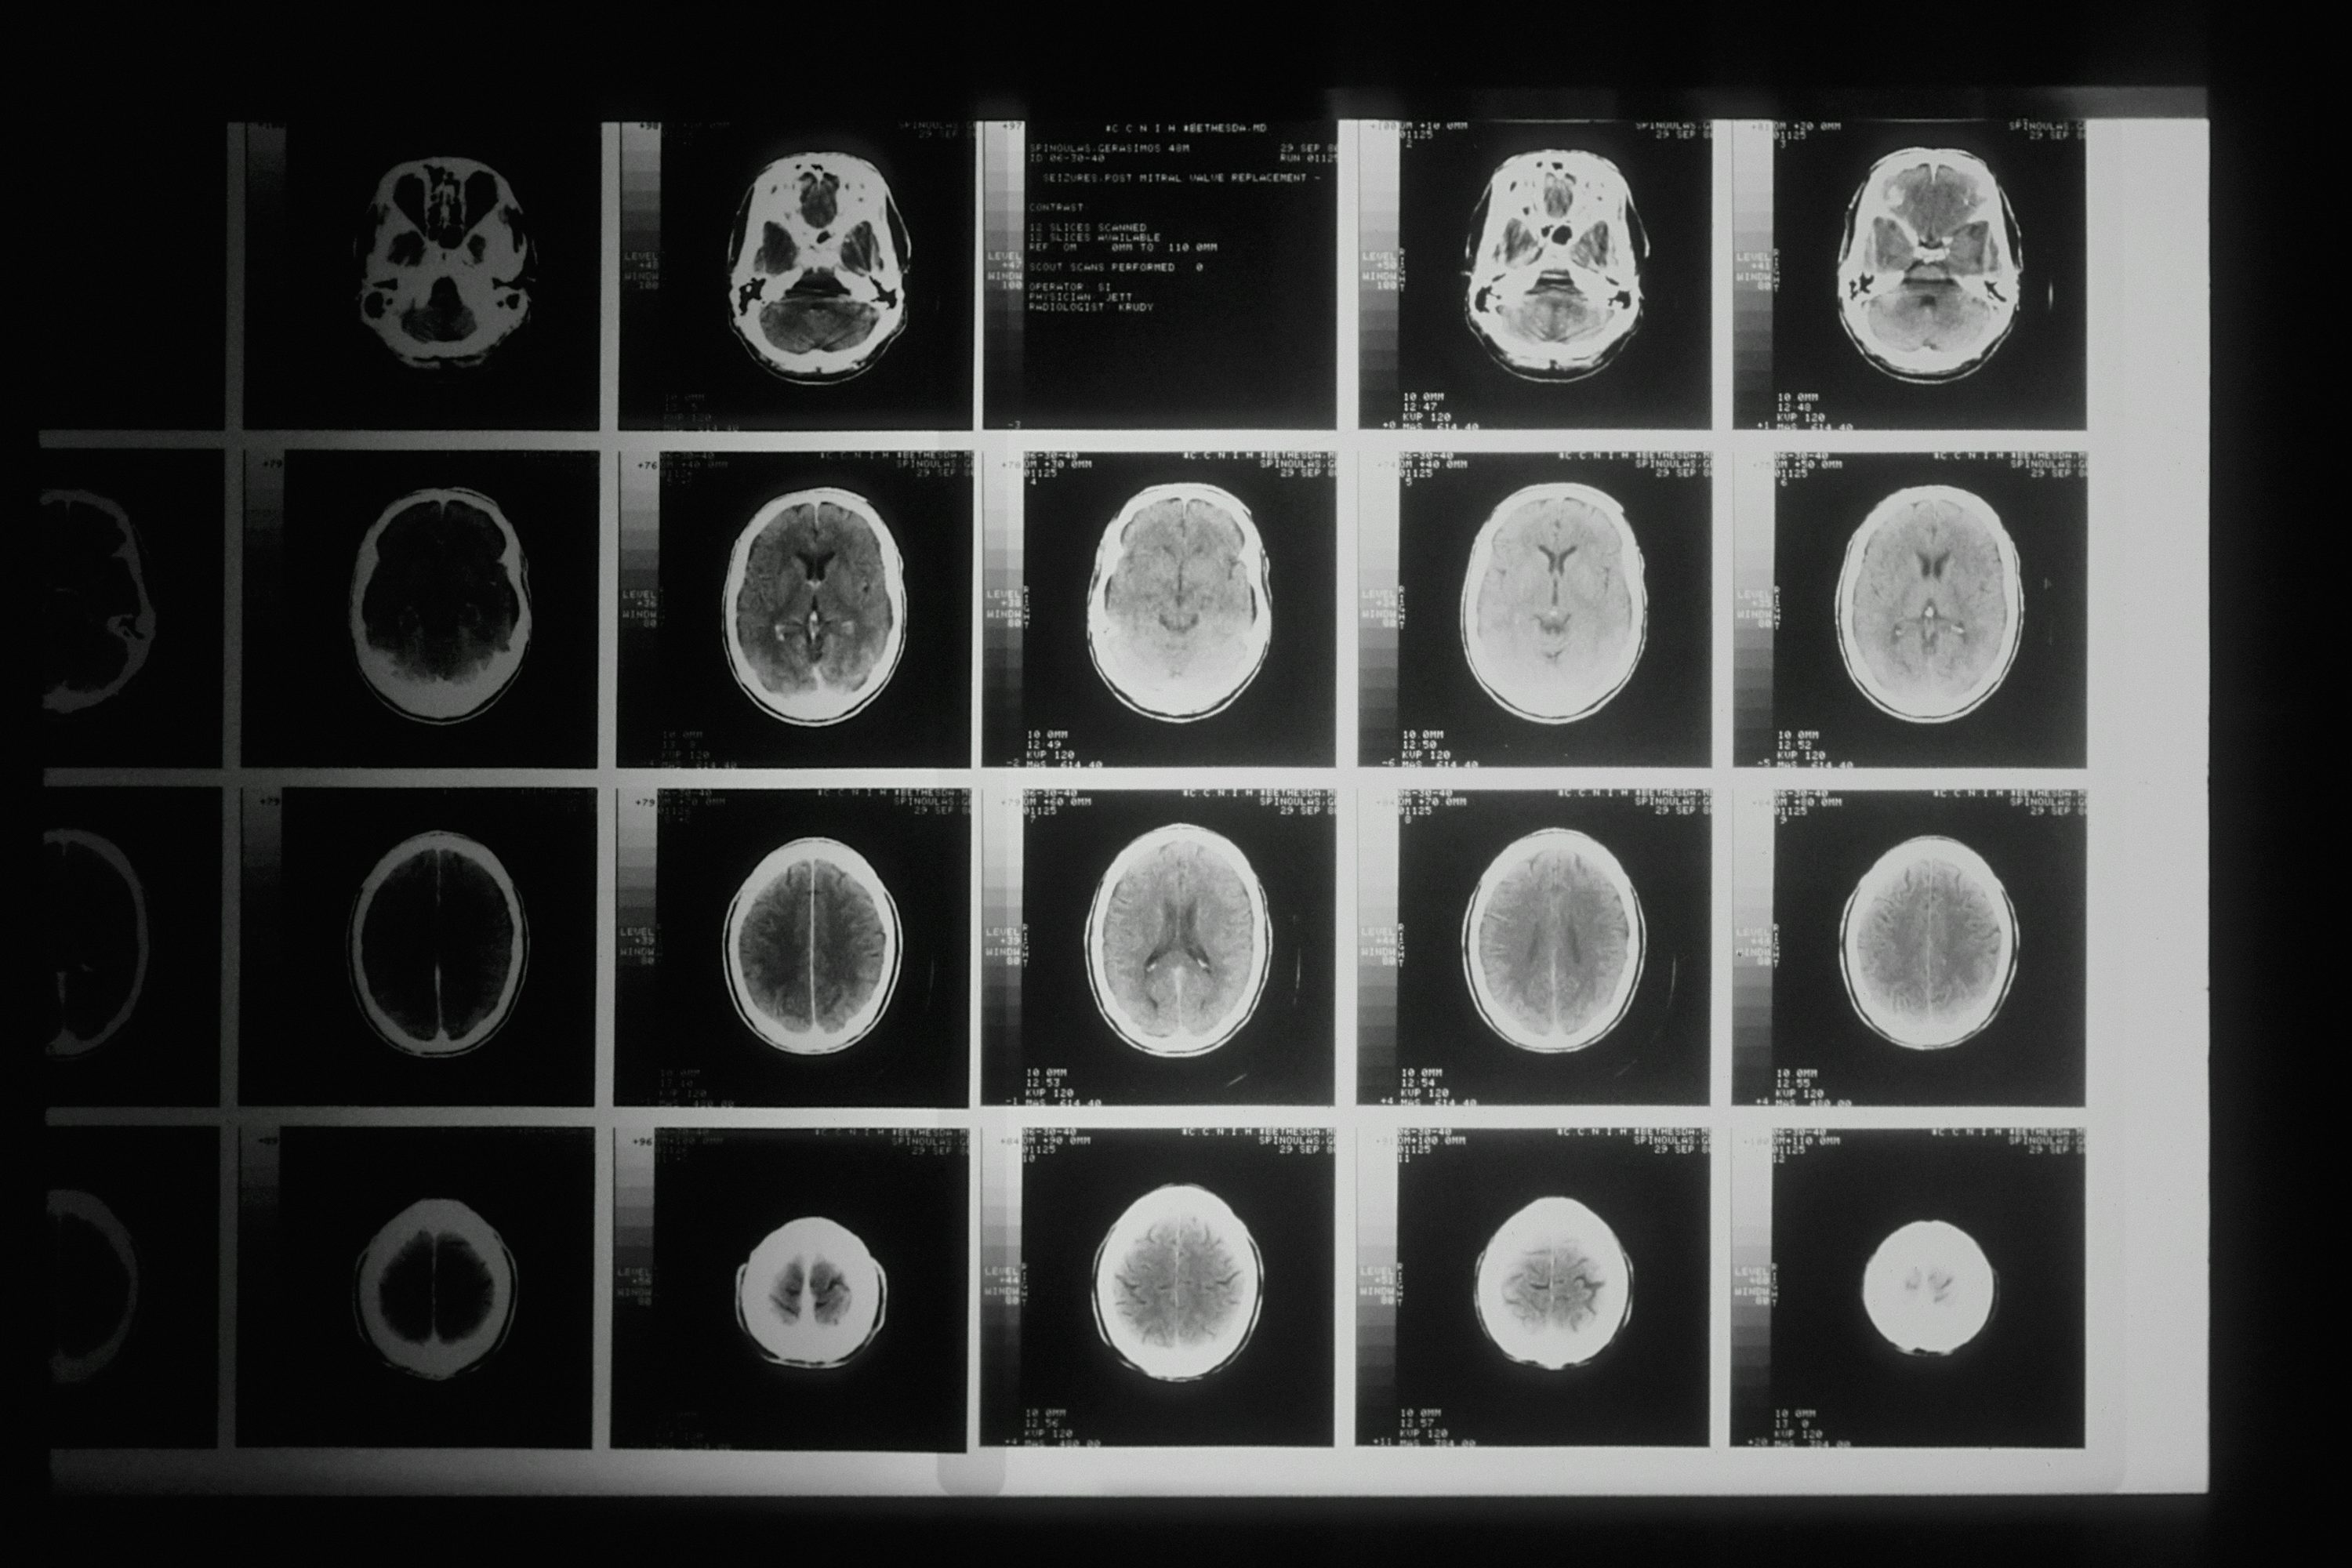

뇌출혈 전조증상 총정리

갑자기 찾아온 심한 두통을 그냥 피곤해서 그런가 보다 하고 넘기신 적 있으신가요? 한쪽 팔에 힘이 빠지는데도 잠깐 저린 거겠지 하고 무시하셨나요? 뇌출혈은 골든타임 3시간을 놓치면 사망하거나 평생 장애를 안고 살아야 합니다. 하지만 대부분의 뇌출혈 환자는 발병 전 명확한 경고 신호를 보냅니다. 문제는 이 신호를 알아채지 못하거나 대수롭지 않게 넘긴다는 것입니다. 뇌출혈 전조증상을 정확히 알고 있다면 소중한 생명을 구할 수 있습니다. 지금부터 절대 놓쳐서는 안 되는 뇌출혈 전조증상 6가지와 발견 즉시 취해야 할 행동을 알려드립니다.갑작스러운 극심한 두통뇌출혈 전조증상 중 가장 대표적이고 중요한 신호는 갑작스러운 극심한 두통입니다. 환자들은 "머리를 망치로 맞은 것 같다", "평생 경험한 적 없는 최악의 두..